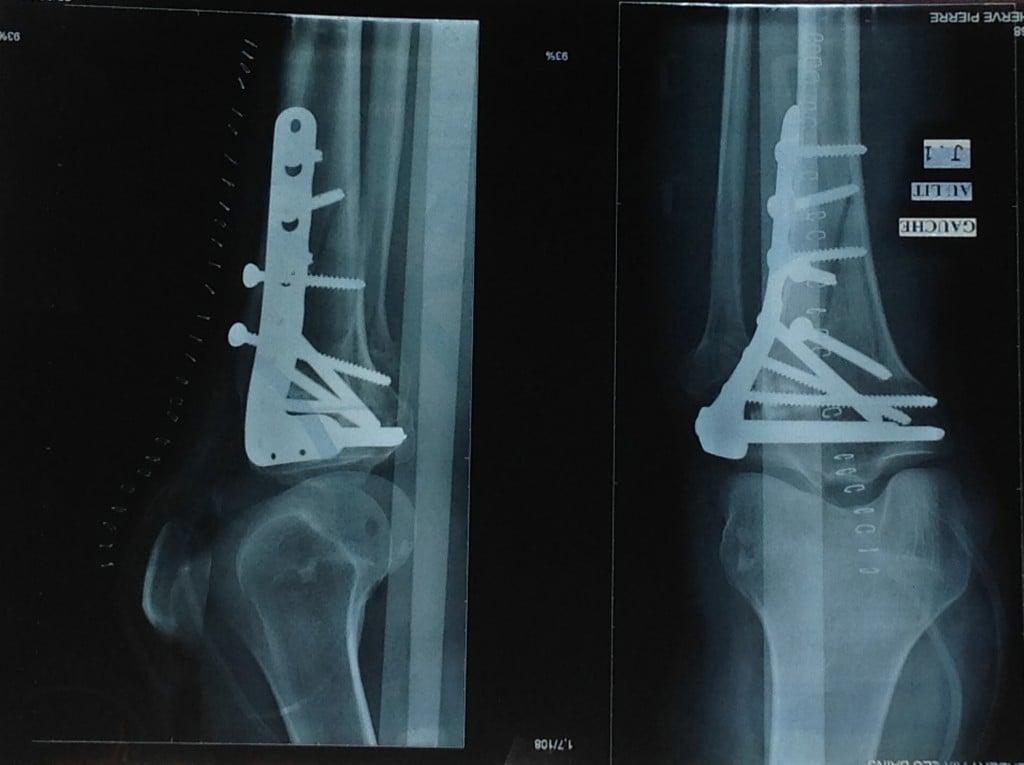

In an incredible three-hour surgery, Dr. Helfet reconstructed my shattered knee cap into no fewer than 20 pieces. Eleven months later, after a flawless recovery, Dr. Helfet and I decided to remove the 10 screws and plate. Once again, he successfully navigated surgery on my genetically fragile bone.